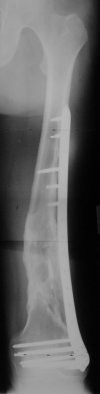

I presented a series of ~25 such cases at EuroTrauma'2004. Many cases were discussed here. I attach am example. Look also recent cases at http://www.hwbf.org/hwb/conf/alex58/scfx.htm,

http://www.hwbf.org/hwb/conf/alex63/alex63.htm

- Your last posted case: how is possible to have secure fixation with applied construct without additional casting, bracing or Ilizarov?

At that moment we had in stock only the 10 mm solid nails so of course there was no idea about early weight bearing. But it was quite enough for early knee ROM excersises (see attached). Two locking screws through the distal block provided that.